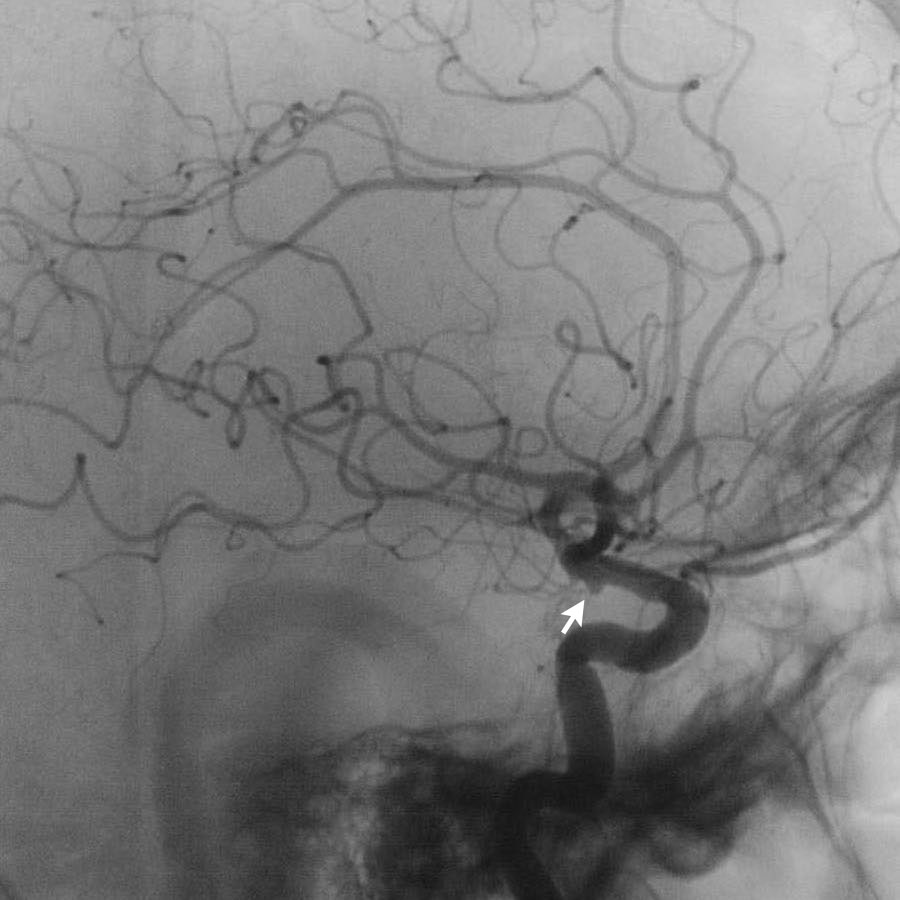

Hình ảnh CT của bệnh nhân SAH tự phát.

CTA được thực hiện để tìm kiếm phình động mạch.

Tiếp tục với DSA…

Lưu ý có hai túi phình động mạch (mũi tên):

- Xoang cảnh (carotid siphon)

- Động mạch não giữa

Cả hai đều được điều trị bằng can thiệp nút coil.